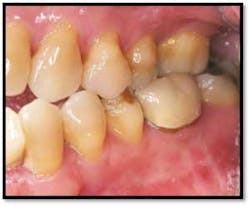

UL/LL reflected in a mirror and UL/LL radiograph

Tissue is light pink, tight and firm. All pockets are 1-3mm, no BOP

LR lingual post Tx and LL lingual post

Tissue is light pink, tight and firm. Pockets 1-3mm no BOP